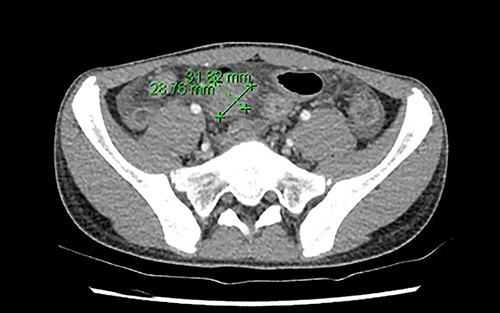

A multi-disciplinary team comprising of surgical, immunology and gastroenterology teams were involved in his care. He was commenced on conservative management with intravenous antibiotics, intravenous immunoglobulin, nil by mouth and total parenteral nutrition for 2 weeks, followed by a slow upgrade in diet for the following 2 weeks. Unfortunately, his pain did not completely resolve, and progress Positron Emission Tomography-CT identified ongoing inflammation in the terminal ileum and further to the rectosigmoid junction (Fig. 2).

Increased metabolic activity in the terminal ileum and anterior to the rectosigmoid junction to the right of midline.